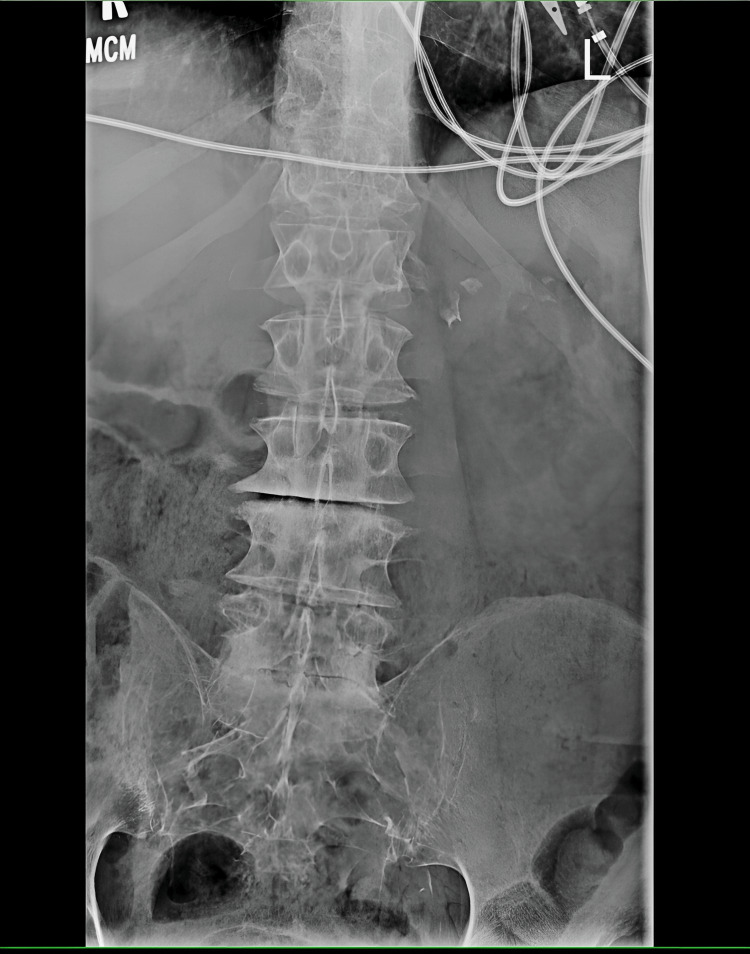

Plain films of the lumbar spine were done on this admission, which showed lumbar spine degenerative disc disease but no compression deformities or likely etiology of his acute weakness (Figure 2).